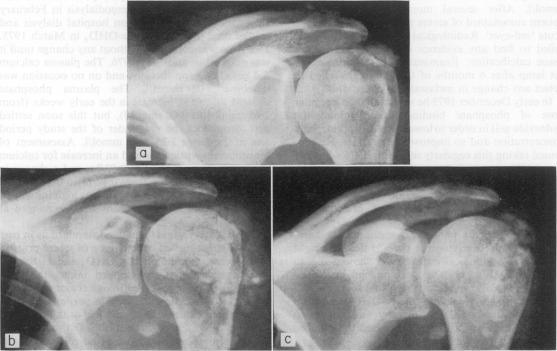

Two cases are reviewed, both of which developed tumoral calcinosis whilst receiving 1, alpha-hydroxy-cholecalciferol therapy. Tumoral calcinosis is an extreme form of peri-articular calcification, and its occurrence in patients with chronic renal failure is unusual. These peri-articular masses developed around the shoulders in both patients, and the action of 1, alpha-hydroxycholecalciferol as a possible factor promoting this form of metastatic calcification is discussed.

本文回顾了两例病例,这两名患者在接受1α-羟基胆钙化醇治疗期间均出现了肿瘤性钙化。肿瘤性钙化是关节周围钙化的一种极端形式,在慢性肾衰竭患者中并不常见。两名患者的肩部周围均出现了这些关节周围肿块,并讨论了1α-羟基胆钙化醇作为促进这种转移性钙化形式的可能因素所起的作用。